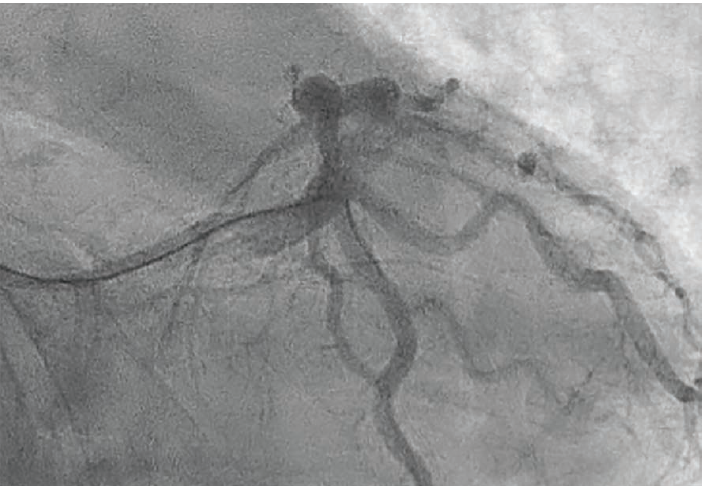

Right radial artery access was obtained using a radial 6 Fr, 10 cm length Glidesheath Slender® Introducer Sheath (Terumo Interventional Systems). We accessed the LV cavity with a 5 Fr, 100 cm length radial Tiger 4.0 catheter (Terumo Interventional Systems), recording an LV end-diastolic pressure of 6 mmHg. The ostia of the right coronary artery (RCA) and left main coronary artery (LMCA) were sequentially engaged using the same Tiger catheter. The diagnostic coronary angiogram revealed a large caliber and dominant RCA with an anterior take-off, showing a proximal RCA stenosis of 25%-30% and minor luminal disease in the mid RCA. The ostial LMCA, a large caliber vessel, displayed 25% stenosis. The left anterior descending artery (LAD), also a large caliber vessel, had a 30%-40% eccentric stenosis in its mid segment, with small to medium diagonal branches showing no obstructive disease. The left circumflex artery (LCx) exhibited a focal 90% stenosis after the take-off of a large caliber obtuse marginal branch (OM) artery (Figure 1).